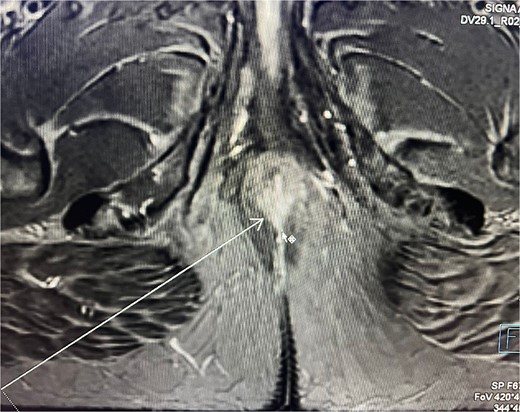

Consequently, an abdominal and pelvic magnetic resonance imaging (MRI) was performed (Fig. 4), which revealed a 16 x 22 mm mass in the perianal region, characterized by asymmetric thickening affecting both the external and internal sphincters, just at the anodermic junction, with extension into the elevator ani muscles.

Abdominal and pelvic magnetic resonance imaging. The white arrow points to a 16 x 22 mm mass in the perianal region, where asymmetric thickening affecting both the external and internal sphincters is evident, located just at the anodermic junction and extending into the levator ani muscles.